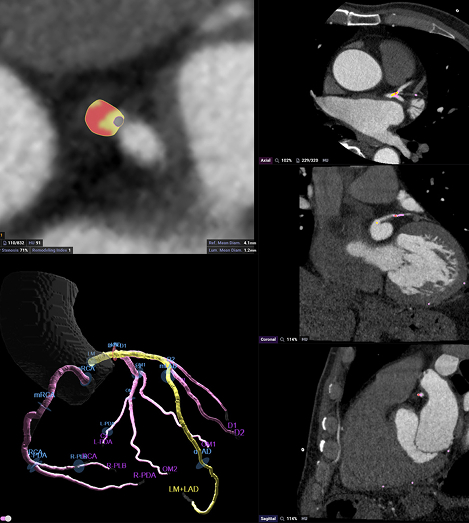

Your images are run through Cleerly® and HeartFlow® – the same FDA-approved tools used by top cardiologists. These advanced AI programs detect and measure all three types of plaque and assess how well blood is flowing through your arteries.

Two board-certified, specialty-trained radiologists interpret your results—giving you a clear, color-coded 3D map of your heart and arteries. You’ll know exactly what’s going on inside, down to the tenth of a millimeter.

Our ultra-low radiation technology that captures your entire heart in one beat. We use Cleerly® and HeartFlow® AI to create a color-coded 3D map of your heart that shows plaque, blood flow, and risk down to a tenth of a millimeter.

✔ 3D map of all plaque types and real-time blood flow